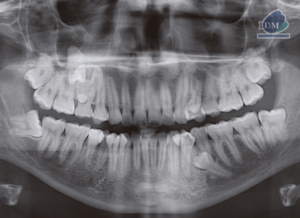

Paciente femenino de 39 años de edad, es referido al Instituto de Diagnóstico Maxilofacial – IDM para evaluación general.En la radiografía panorámica (Figura 1), se